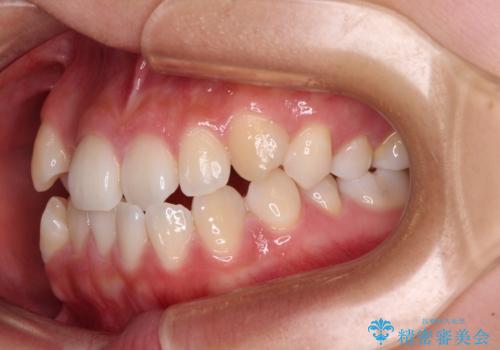

- 前歯のデコボコを治したいとのことで来院された患者様です。

インビザラインによるマウスピース矯正も適用となる歯列でしたが、できる限り楽して、短期間で治したいとのことで、ワイヤー装置にて矯正治療を行うこととしました。